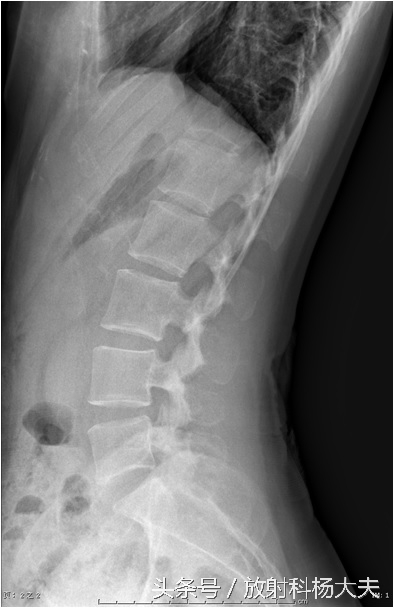

先拍片子吧,看看骨头有没有问题。

片子拍了,很好,没有任何问题,没有骨质破坏,没有骨刺,椎间隙也不窄。